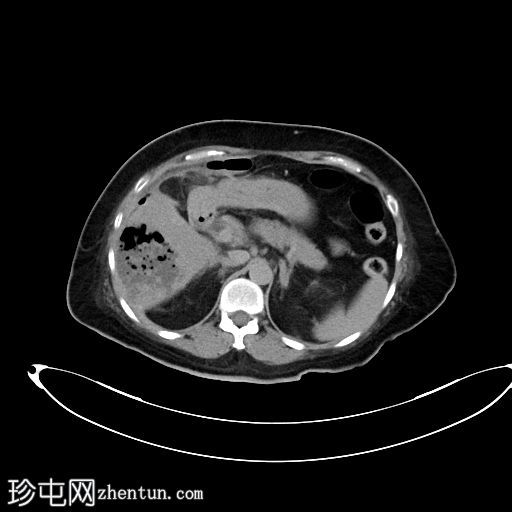

CT

轴位

非增强

肝段 6 和 7 可见多房性积液,呈环状强化

积液内可见多个气体腔

破入肝包膜下间隙,可见肝包膜下积液及气体腔

壁层腹膜与前腹壁之间可见另一局灶性积液

肝段 7 的肝内胆管局灶性扩张(0.3cm),内含气体腔

其他肝内胆管和肝外胆管均正常

胆囊缺失,可能由于既往胆囊切除术所致

无游离液体。

双侧肾皮质囊肿

轻度右侧胸腔积液伴邻近肺不张